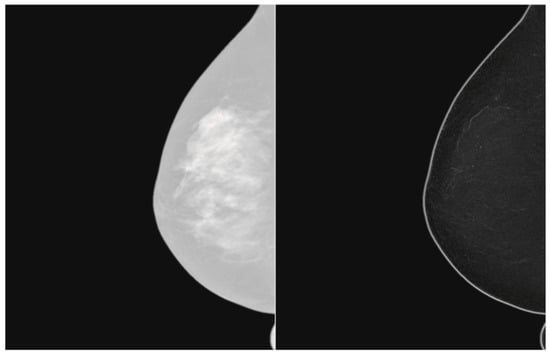

Filtering of Mammograms Based on Convolution with Directional Fractal Masks to Enhance Microcalcifications

1. Introduction